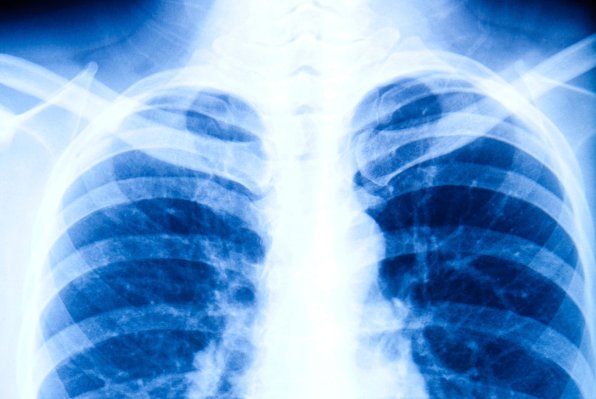

Jedite ga samo dva puta tjedno i prepolovit ćete rizik od opasnog raka. Jedete li sirov češnjak dva puta tjedno, mogli biste gotovo prepoloviti rizik od razvoja raka pluća, pokazuje nova studija. Studija provedena u Kini pokazuje da odrasle osobe koje redovito konzumiraju sirov češnjak imaju 44 posto manje izgleda dobiti rak pluća.

Čak i kad su znanstvenici uzeli u obzir u pušenje – najveći pojedinačni uzročnik raka pluća – uočili su da češnjak još uvijek smanjuje opasnost za nekih 30 posto. Pušenje uzrokuje najmanje 80 posto slučajeva raka pluća, a pet godina nakon dijagnoze preživljavanje je manje od 10 posto.